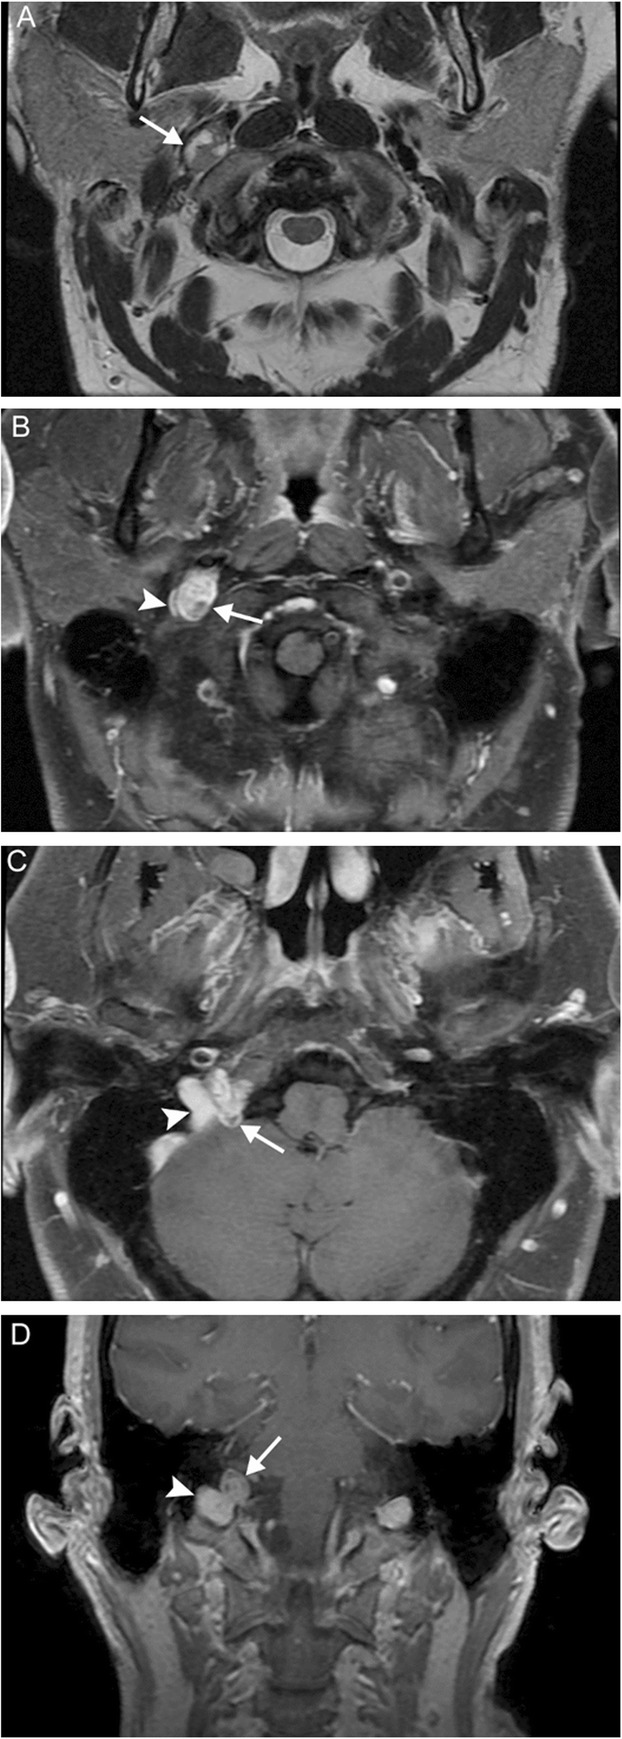

Fig. 13.

Jugular paraganglioma. A 55-year-old woman with relatively sudden onset hoarseness and dysphagia to liquids, who was found to have right vocal cord paralysis on laryngoscopy. Coronal T2 (a) and axial T1 post-contrast (b) MR images reveal a T2-isointense, avidly-enhancing lesion at the right jugular fossa (arrows) extending intracranially, with mild mass effect upon the right cerebellar hemisphere. Foci of low signal (“pepper”) represent flow voids, reflecting hypervascularity. Based on location and appearance, findings are consistent with a jugular paraganglioma (glomus jugulare tumor)

Fig. 14.

Vagal paraganglioma. A 67-year-old man presenting with raspy voice. Sagittal T1 post-contrast (a), axial T1 (b), and axial T2 (c) MR images reveal a T1-hypointense, avidly enhancing lesion with heterogeneous areas of high T2 signal (arrows) centered within the left carotid space. The internal carotid artery is displaced anteromedially (arrowheads). Pathology was consistent with a vagal paraganglioma (glomus vagale tumor)